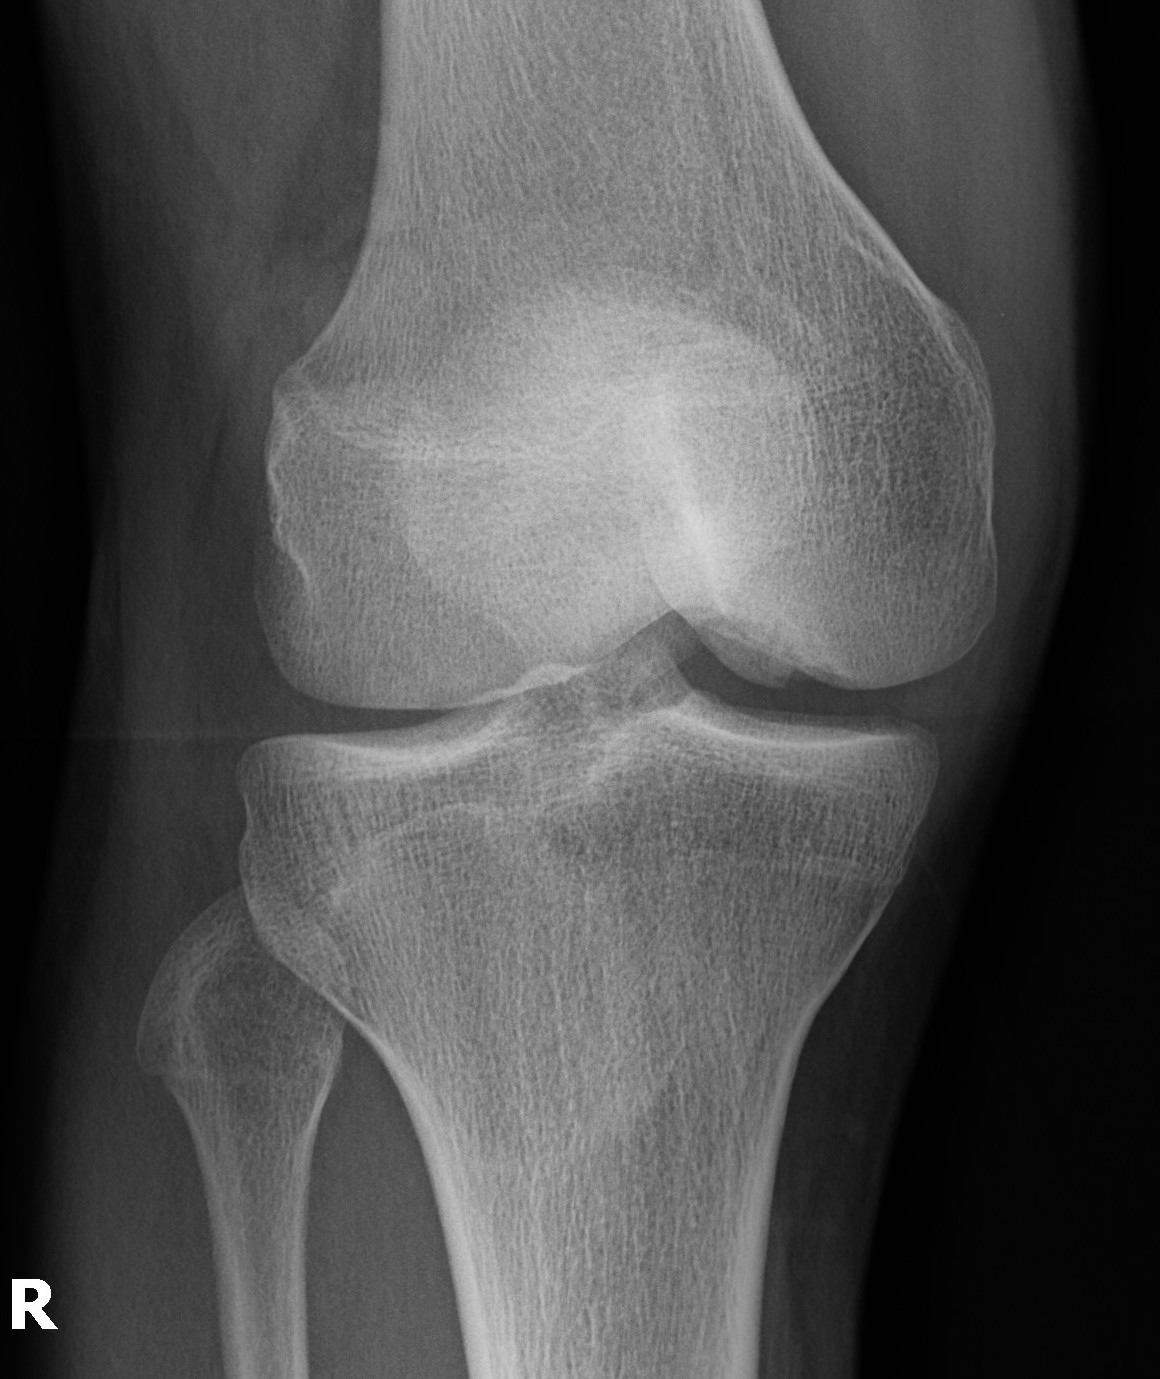

Stable lesion with no cysts Stable lesion with cysts